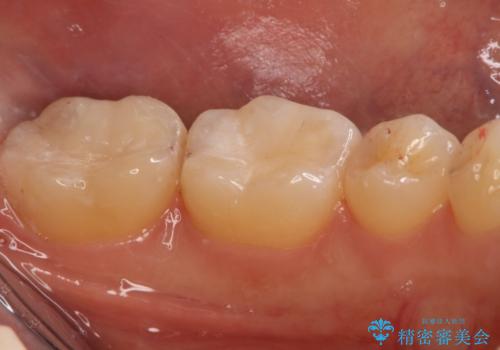

- 左下6、7番の虫歯をセラミックにて治療を希望された患者様です。

切削量を考慮してセラミックインレーを選択しました。

7番は虫歯が深かったのでCR裏層した上で形成、印象をしています。